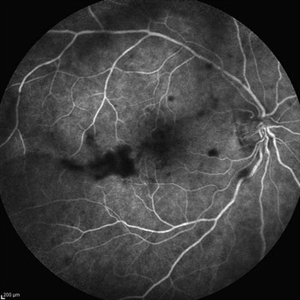

Behcet's Disease Behcet's DiseaseMar 13 2013 by Hamid Ahmadieh, MD Late phase FA of the right eye of a 23-year-old man with retinal vasculitis and branch retinal vein occlusion (BRVO) due to Behcet's disease . Photographer: Solmaz Shahmohammad, Negah Eye Center, Tehran Imaging device: Heidelberg Spectralis Condition/keywords: branch retinal vein occlusion (BRVO), retinal vasculitis

Behcet's Disease Behcet's DiseaseMar 13 2013 by Hamid Ahmadieh, MD Wide field FA of the right eye of a 23-year-old man with retinal vasculitis and branch retinal vein occlusion (BRVO) due to Behcet's disease . Photographer: Solmaz Shahmohammad, Negah Eye Center, Tehran Imaging device: Heidelberg Spectralis Condition/keywords: branch retinal vein occlusion (BRVO), retinal vasculitis